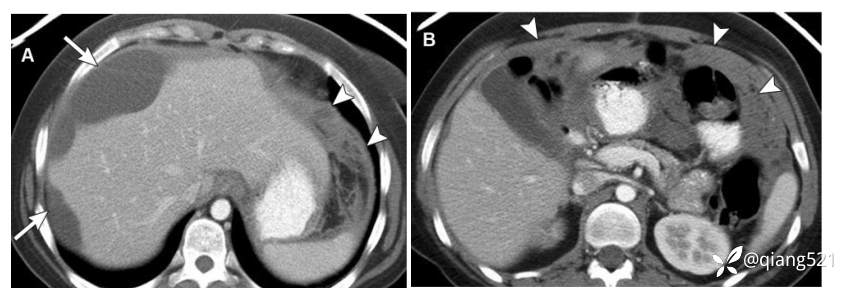

一例43岁女性左卵巢成熟畸胎瘤切除术后腹膜胶质瘤病。A、B经腹部的轴向CECT显示腹膜肿块样增厚(箭头)和复杂的腹腔内积液,导致肝缘呈扇形(箭头)。